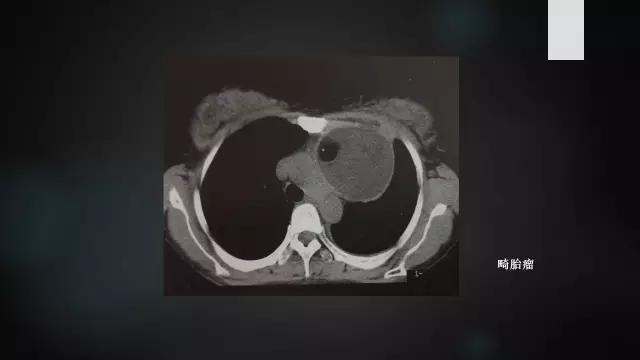

2.CT表现:前纵隔内边缘光滑的厚壁囊性肿块,囊壁常有钙化,病灶内密度不均匀,囊内出现脂肪、脂液平面、骨骼、牙齿等为特征性表现。少数病灶以软组织成分为主,形成实性畸胎瘤。如出现周围脂肪层不清、邻近结构受累,则提示恶性畸胎瘤可能。

3.MRI表现:肿瘤内出现脂肪、水、软组织的混杂信号,钙化、骨骼、牙齿等呈低或无信号。